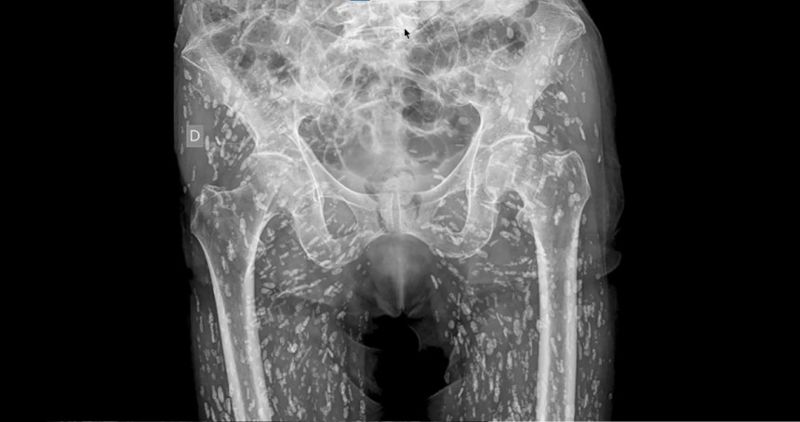

지난 22일(현지시각) 더 선에 따르면 샘 갈리 박사는 자신의 SNS에 "내가 본 가장 충격적인 엑스레이"라며 한 남성의 엑스레이 사진을 올렸다.

엑스레이 사진을 보면 이 남성의 하반신에는 하얀 좁쌀 같은 기생충 알 수백 개가 가득 차 있었다.

해당 남성은 엉덩이에 통증을 느껴 병원을 찾았고, 엑스레이 검사 중 유구낭미충증(Cysticercosis)에 감염됐다는 진단을 받았다. 낭미충증은 날고기나 덜 익힌 돼지고기를 섭취했을 때 위장에 기생하게 되며 발병된다.

샘 갈리 박사는 "기생충은 체내 어디로나 이동할 수 있다”며 “기생충이 뇌로 옮겨가면 문제가 매우 심각해진다”라며 "날것이나 덜 익힌 돼지고기를 먹었을 때 감염될 가능성이 높다"고 설명했다.